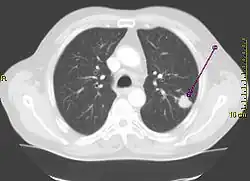

CT-Thoraxaufnahme (axiales Schnittbild) -